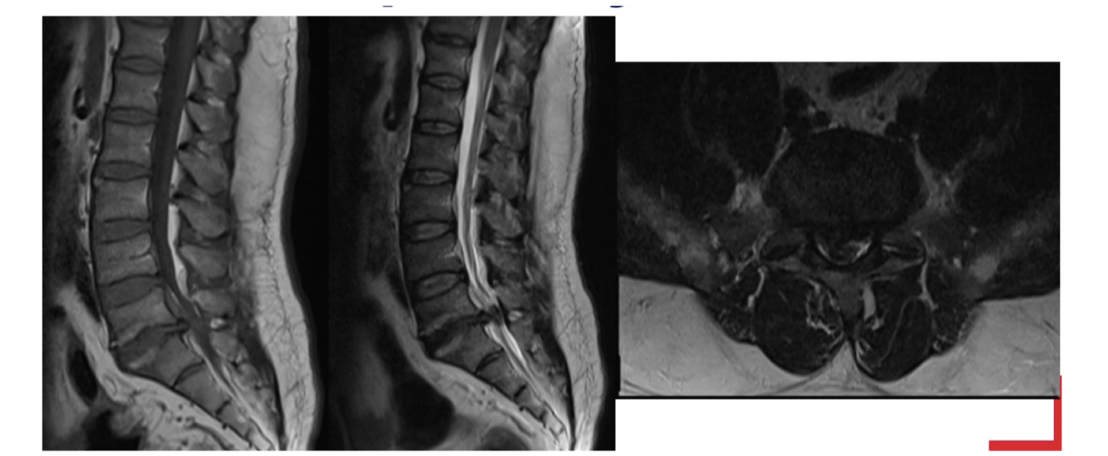

Sequence + Pathology?

T1,T2

• Cauda Equina syndrome

• L5/S1 disk space herniation compressing the cauda equina.

• Signal intensity is lost in T2 sag as you get to L5/S1 disk space.

Sequences + pathology?

• Axial=T2,1st sag=T1,2nd sag=T2

• Anterior disk bulge of L3/4 and L4/5 disks

• Anterior longitudinal ligament has lost its normal shape as it is being pushed

anteriorly by the disk bulges.